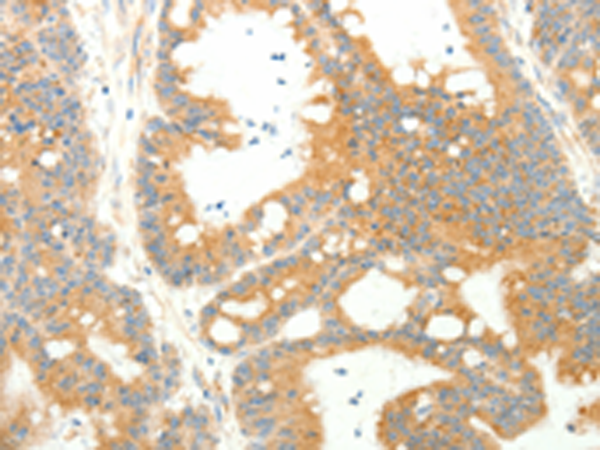

分类: 科研抗体货号: P11198别名: ARC20; P20-ARC应用: WB,IHC反应种属: Human, Mouse